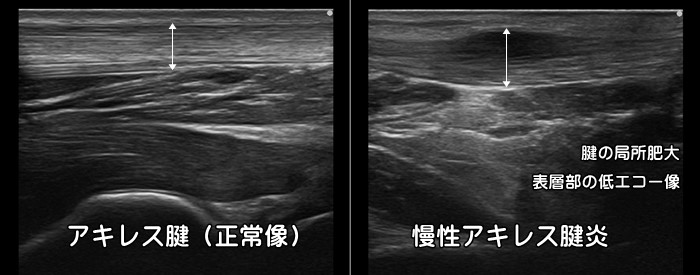

慢性アキレス腱炎

慢性アキレス腱炎の場合は腱が肥厚し表層部に低エコー像がみられます。

慢性アキレス腱炎により組織の変性がおこるとアキレス腱断裂を発症するリスクが高まります。